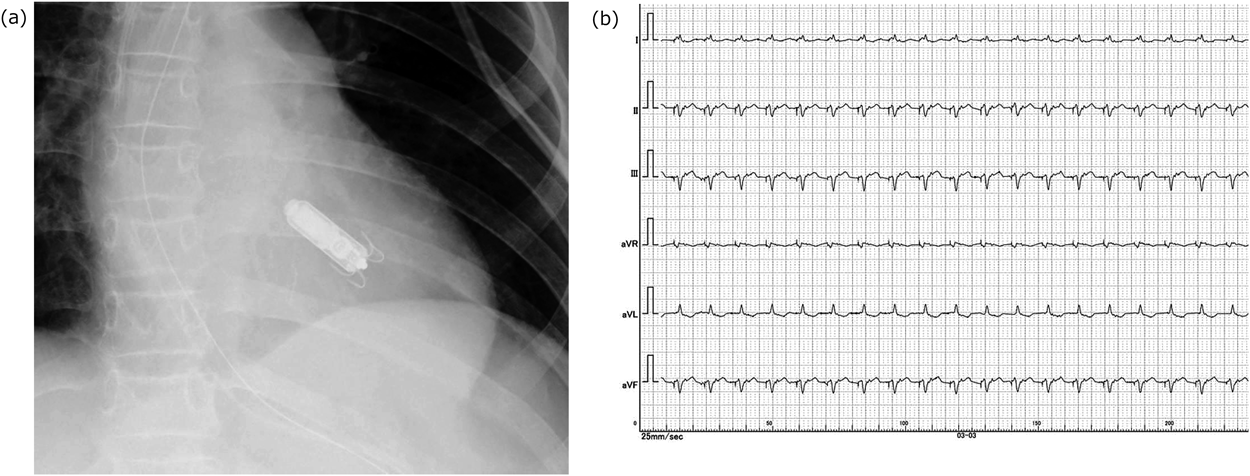

Fig. 4 Post implantation test

(a) Chest X-ray demonstrated final position of leadless pacemaker. (b) Limb lead electrocardiogram showed waveforms with LPM pacing. QRS was wide (170 msec).